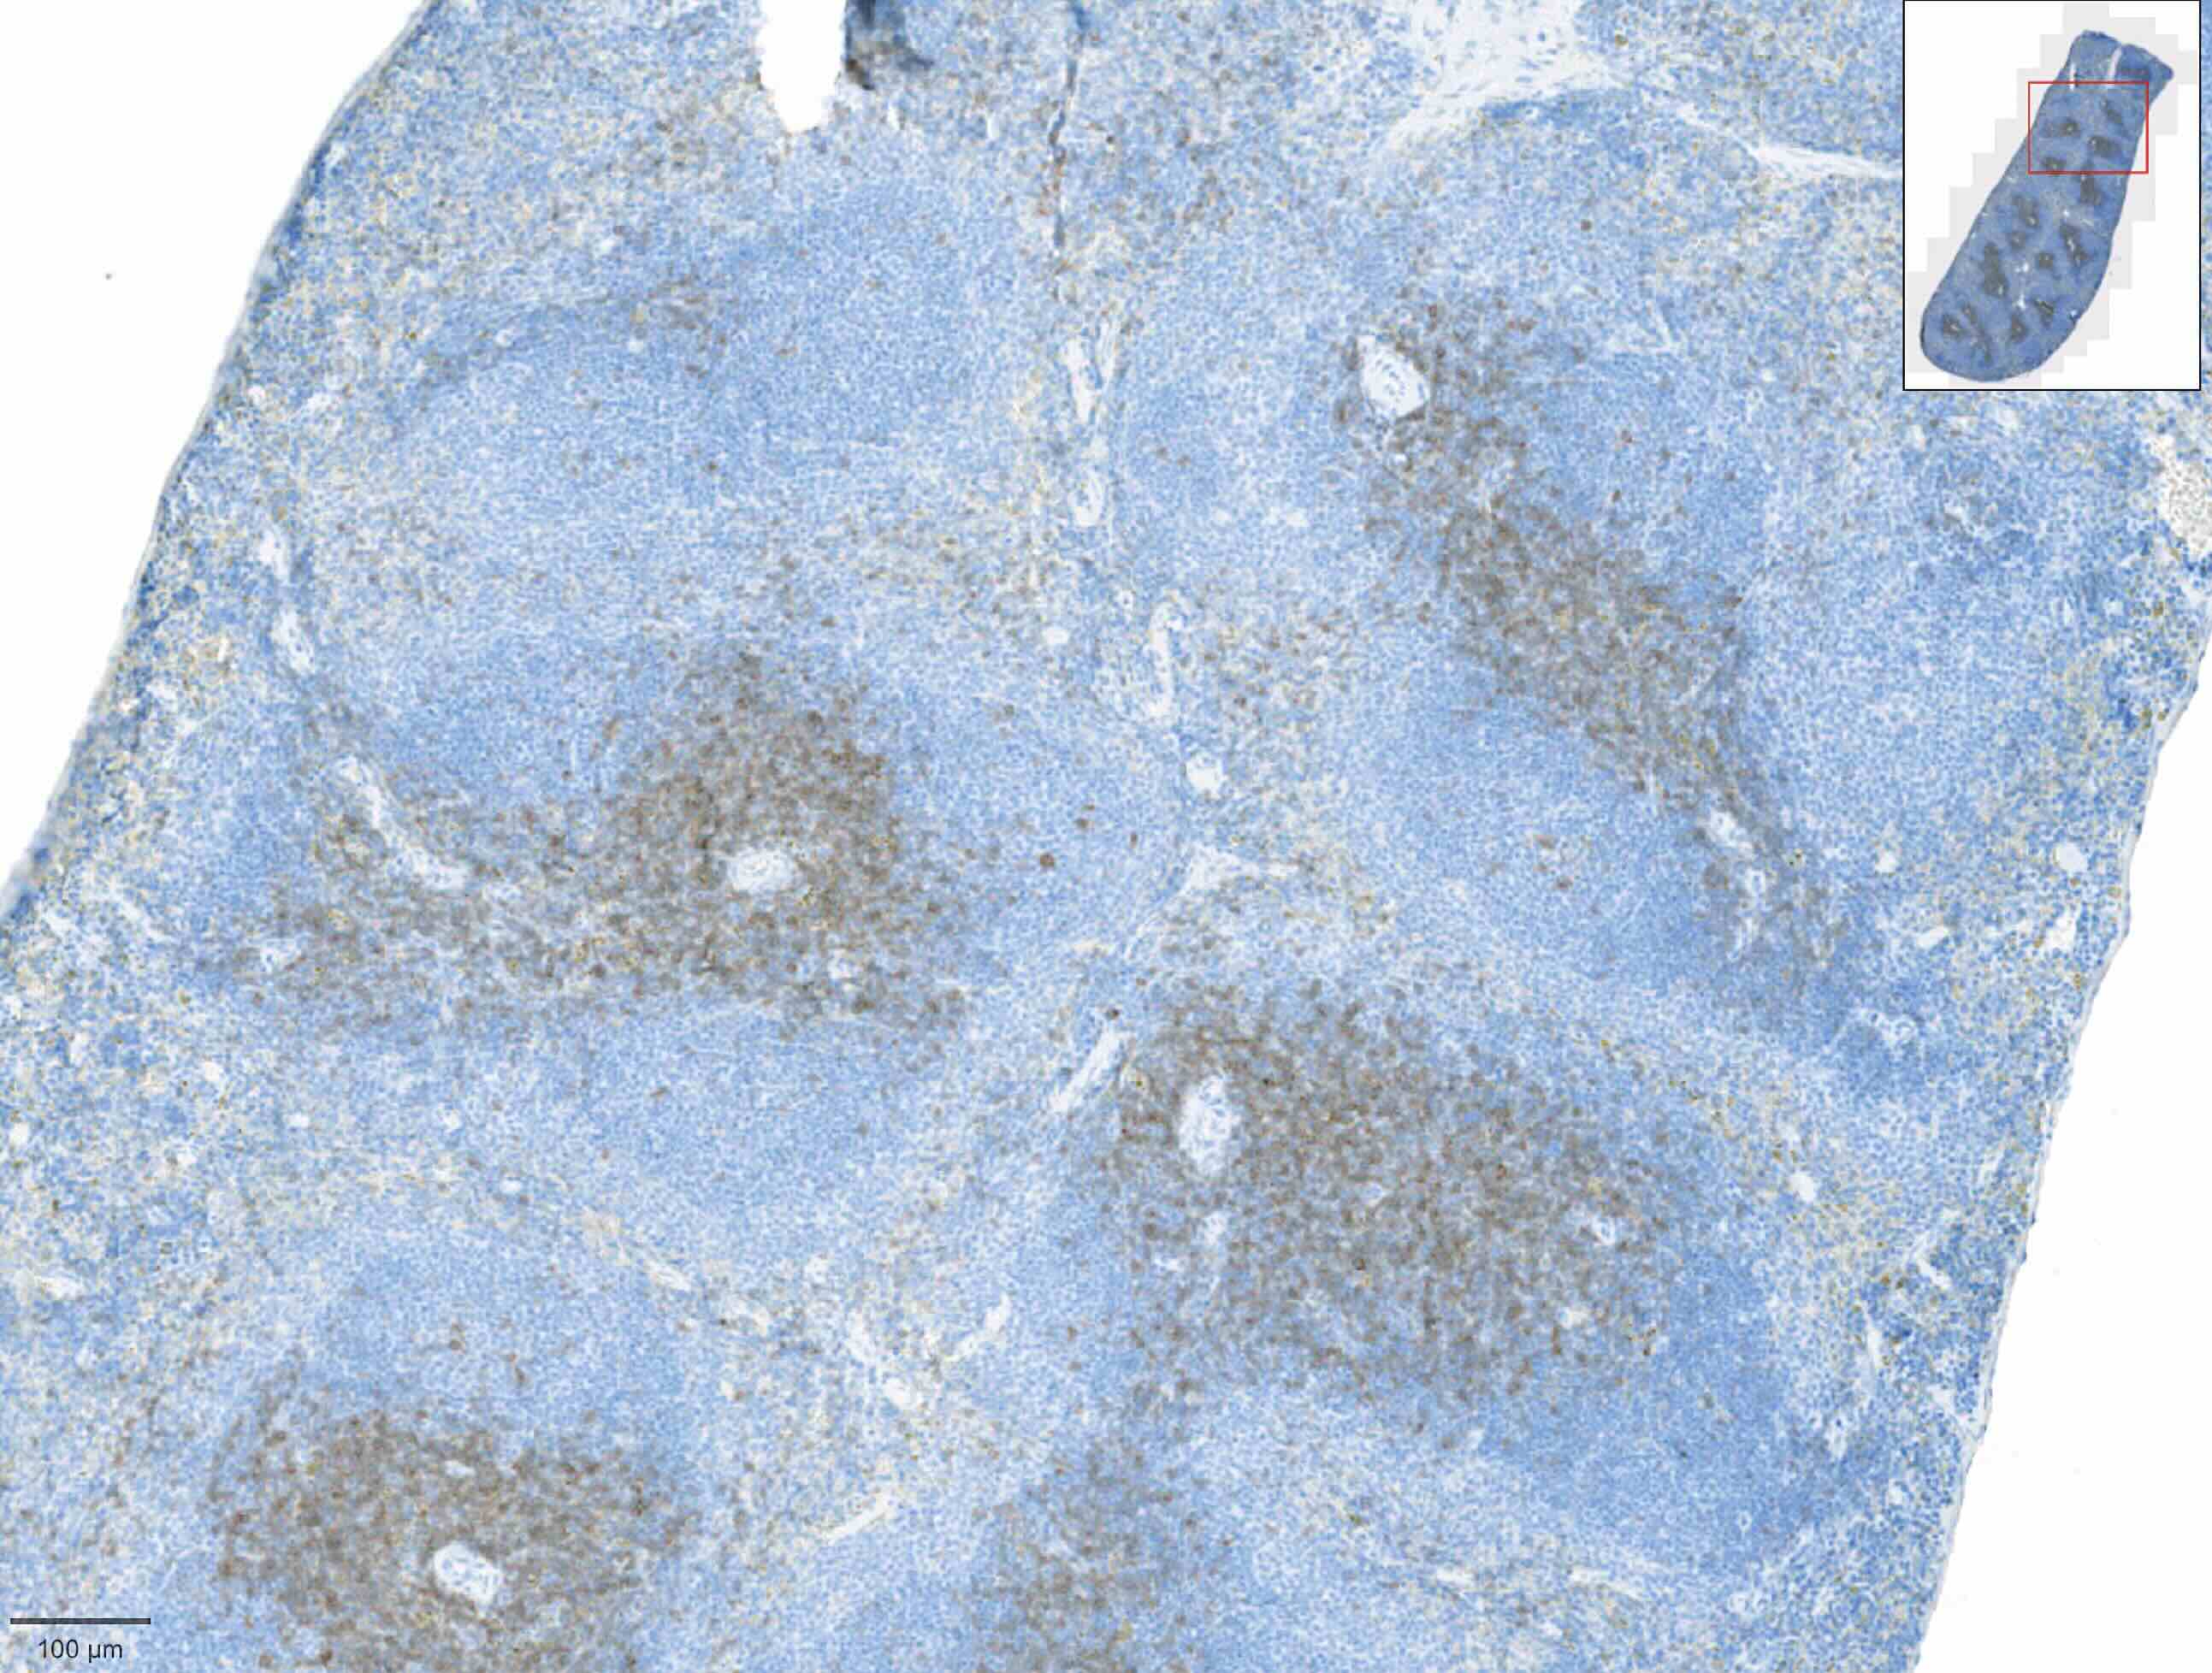

Matériel biologique testé Anticorps testés | Rate | Rate | Rate |

Rate Non validé | |

Rate Validé | |

Rate Validé |